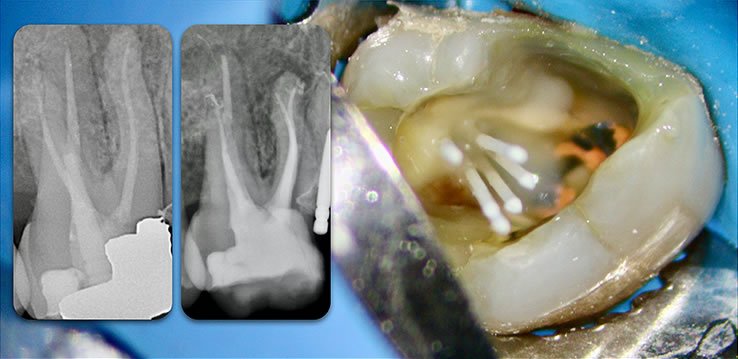

Template for x-rays

Biolight® DRILL-FREE posts are available in bundles of 4, 6, 9 and 12 strands. The post size is selected based on the width of the canal at the coronal area. Depending upon the canal width at the apical stop, a certain number of strands must be pushed to the stop. Both of the measurements are made with the assistance of a radiograph and the template that is included in the TRAINING KIT.